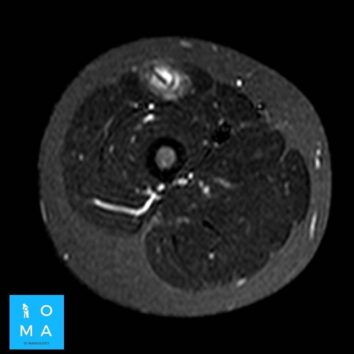

🔹Varón de 12 años que consulta por tumefacción en región anterior de muslo derecho. Refiere molestia a ese nivel 3 días antes, después de pique en partido de fútbol.

🔹Cambios inflamatorios asociado a edema y banda líquida que rodea a la unión miotendinosa central del sector medio del músculo recto anterior del cuádriceps derecho, de 10 mm de extensión, evocador de desgarro de la unión miotendinosa grado II.

🔹En un segundo tiempo se realiza ecografía dirigida, confirmando los hallazgos a nivel del tendón central del músculo recto

anterior del cuádriceps derecho, presentando desgarro grado II, asociado a un

aumento del flujo vascular al examen Power doppler.